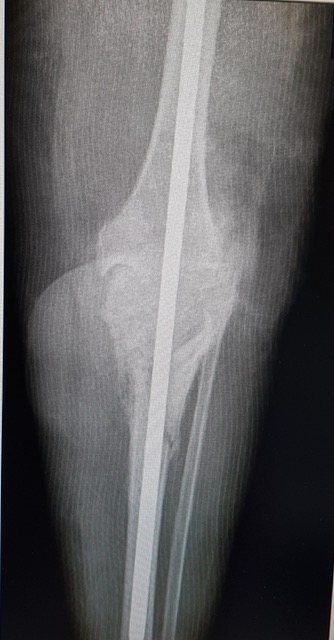

Medicii Spitalului Județean Sibiu au realizat ieri o operație rară, cu un grad mare de complexitate. Este vorba despre artrodeza de genunchi fixată cu tija centromedulară blocată, care a necesitat un transplant osos.

„A fost o operație extrem de complexă, care a solicitat la maxim echipa chirurgicală. Am operat o femeie cu un context medical mai aparte, care a prezentat un defect osos important la nivelul genunchiului, după câteva intervenții chirurgicale/traumatisme din trecut. Intervenția, care a necesitat o pregătire preoperatorie foarte bună, atât medicală cât și administrativă, a decurs foarte bine. Ea reprezintă însă doar o primă etapă în vindecarea pacientei. Urmează o fază postoperatorie dificilă și apoi o recuperare lungă care, speram noi, se va încheia cu un rezultat pozitiv pentru pacienta noastră“, a declarat dl Conf. Dr. Mihai Roman, medic primar ortopedie traumatologie.Intervențiile de artrodeză a genunchiului sunt operații mai rare și necesită un grad mare de experiență precum si o dotare corespunzătoare. De asemenea, necesită acces la grefele osoase furnizate de către Banca de Os. Operația a fost prima intervenție de acest tip din secția de ortopedie a SCJU Sibiu la care s-a realizat un transplant osos după mai bine de 10 ani. În urma rigorilor impuse de legislația europeană, intervențiile de transplant tisular pot fi efectuate doar în centre special acreditate, procedura de acreditare fiind una deosebit de riguroasă. SCJU Sibiu este acreditat pentru activitatea de transplant tisular – utilizare de țesuturi umane(os/tendon/cartilagii) în scop terapeutic, de către Agenția Națională de Transplant.

“Pentru această intervenție am colaborat foarte bine cu echipa condusă de către dl Dr. Andrei Nica de la Agenția Națională de Transplant, căruia doresc sa-i mulțumesc pe aceasta cale pentru colaborarea foarte bună. Grefele osoase pe care le-am utilizat provin din Banca de Os din cadrul Spitalului Colentina București. In urma demersului pe care l-am făcut, acestea au sosit la Sibiu in preziua intervenției printr-un transport special,” a subliniat Conf. Dr. Roman.

Intervenția, care a durat mai multe ore, a fost realizată de o echipă condusă de către Conf. Dr. Mihai Roman și care i-a avut în componență pe Dr. Bocea Bogdan, Dr. Ispas Teofil, Dr. Braniște Alexandru, Asist Presecan Mioara, As. Arcaș Sorin. Echipa de anestezie a fost constituita din Dr. Anca Sorea, Dr. Cotor Simona și As. Claudia Marcuțiu.